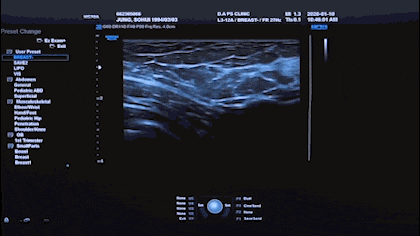

Various medical equipment